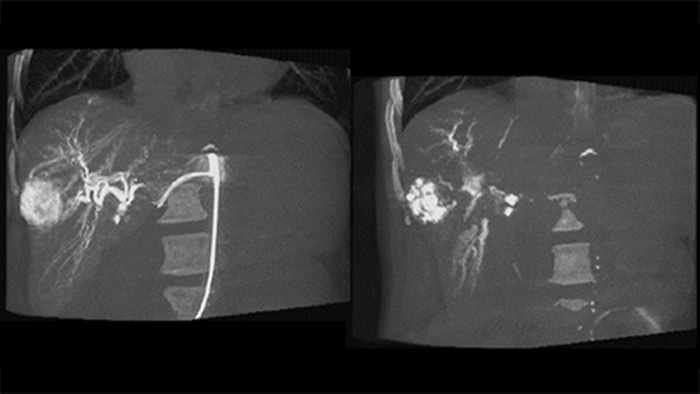

適切な治療を決定するには、肝癌小結節陰影を区別し、小さな栄養血管を特定する能力が不可欠です。病変部のセグメンテーションを行い、すべての栄養血管へとナビゲートすることで成功の機会が増加します。患者がカテーテル寝台の上にいる間に治療エンドポイントと治療の結果を確認できるため、臨床転帰が向上します。

患者の左側のCアーム軌道をずらすことで、CBCT Openでは患者テーブルのオフセンター配置を可能にし、FOVのセンタリングが改善されます³⁻⁴。これにより、画像の収集範囲が拡大し、肝臓周辺の腫瘍の視覚化に役立ちます⁴。